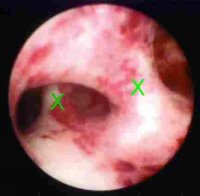

Η ασθενής τοποθετείται σε θέση λιθοτομίας και υπό γενική ή τοπική αναισθησία εισάγεται το υστεροσκόπιο διαμέσου του τραχήλου στην ενδομήτρια κοιλότητα. Γίνεται διαδοχικά επισκόπηση του τραχηλικού αυλού, πανοραμική απεικόνιση της ενδομήτριας κοιλότητας, εντοπισμός των σαλπιγγικών στομίων και ενδελεχής εξέταση όλων των παθολογικών εστιών της ενδομήτριας κοιλότητας.

Ενδείξεις για υστεροσκόπησηΗ κύρια ένδειξη της υστεροσκόπησης είναι η ανώμαλη αιμορραγία της μήτρας, όπου απαιτείται εκτίμηση της παθολογίας της ενδομήτριας κοιλότητας και αποκλεισμός κακοήθειας. Μη φυσιολογική αιμόρροια μπορεί να είναι δυσλειτουργικής αιτιολογίας ή να οφείλεται σε ύπαρξη πολυπόδων , ινομυωμάτων, ξένου σώματος (κυρίως ενδομητρίων σπειραμάτων), σε χορήγηση ορμονικής θεραπείας υποκατάστασης σε γυναίκες μετεμηνοπαυσιακής ηλικίας, σε χορήγηση ταμοξιφαίνης ή σε παρουσία καρκίνου του ενδομητρίου. Με την υστεροσκόπηση η διάγνωση όλων αυτών των καταστάσεων γίνεται ευχερώς και με ακρίβεια υπό άμεση όραση, ενώ είναι δυνατή η εστιακή βιοψία, εάν υπάρχει ένδειξη. Η υψηλή ευαισθησία της μεθόδου της καθιέρωσαν ως τον "χρυσό κανόνα" στην διάγνωση των ενδομητρίων παθήσεων και τείνει να αντικαταστήσει την κλασική απόξεση του ενδομητρίου.

Σε περιπτώσεις υπογονιμότητας αποτελεί τη μέθοδο εκλογής τόσο για τη διάγνωση όσο και τη θεραπεία, διότι έχει βρεθεί ότι σε ποσοστό έως και 62% των υπογόνιμων γυναικών υπάρχει παθολογία της ενδομητρικής κοιλότητας. Υπερτερεί σαφώς της υστεροσαλπιγγογραφίας με άμεση διάγνωση των ενδομήτριων συμφύσεων, διαφραγμάτων, ινομυωμάτων, πολυπόδων αλλά και εκτίμηση της κατάστασης του ενδομητρίου. Αποτελεί επίσης σημαντικό εργαλείο στη διερεύνηση των καθ’έξιν αποβολών.